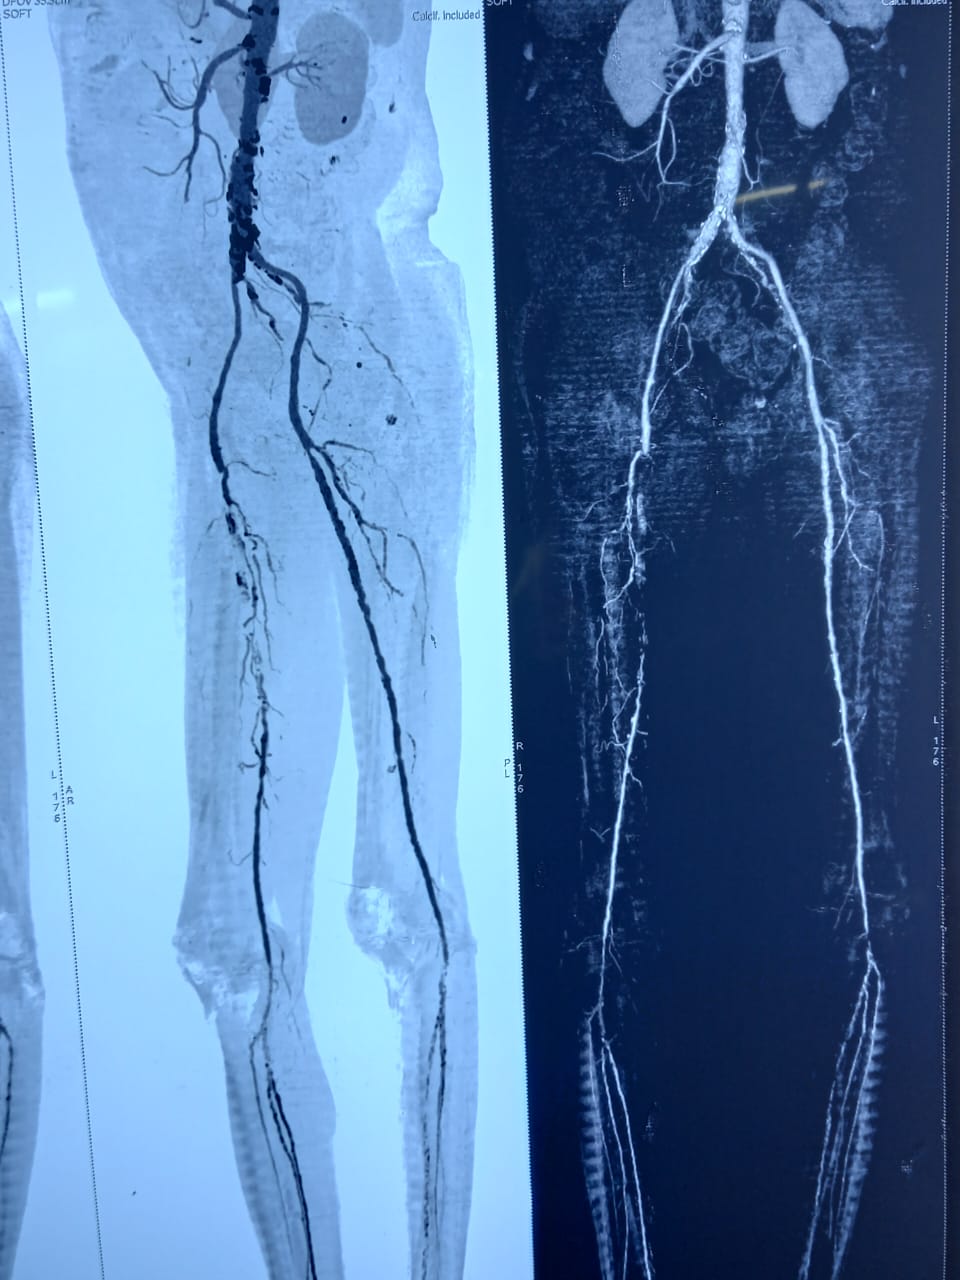

Endovascular Treatment Of Gangrene ( Multi Level Correction)

Right leg critical ischemia grade 5 Hybrid treatment ( right iliac steering + angioplasty then femoro_popliteal bypass) done. Post -op ATA & PTA palpable confirmed on hand Doppler. Patient all symptoms subsides and walk normally.